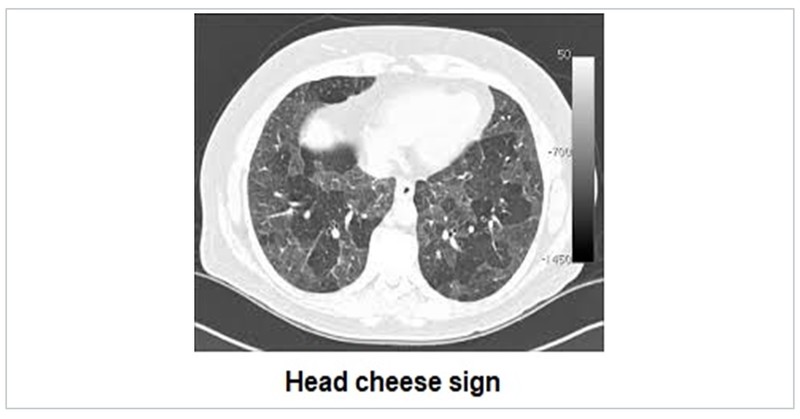

HRCT in ILD is an exhaustive topic in itself. ILD are characterised by interlobular interstitial septal thickening, honeycombing, ground glass opacification and nodules. Idiopathic interstitial pneumonia (IIP) have varied characteristic distribution. Atoll sign is defined as central ground-glass opacity surrounded by denser consolidation and is seen in COP. Sarcoidosis is characterised by fissural nodules and may cause tracheal nodularity. Miliary mottling with randomly scattered nodules in miliary tuberculosis, crazy pavement sign i.e appearance of ground-glass opacity with superimposed interlobular septal thickening and intralobular septal thickening, seen in pulmonary alveolar proteinosis and sand storm sign in pulmonary microlithiasis are some ILD mimics with characteristic CT pattern. The Head Cheese sign consists of juxta-positioning of distinct radiographic areas of low, normal, high attenuation is seen in sub-acute hypersensitivity pneumonitis, sarcoidosis and atypical mycoplasma pneumonias.